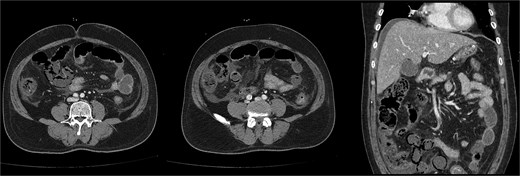

Noncontrast abdominopelvic computed tomography (CT) showed multifocal air foci within the liver and mesenteric vessels, suggesting possible bowel ischaemia (Fig. 1). After surgical consultation, medical management was recommended as DKA was considered the primary cause. The patient was admitted to the intensive care unit (ICU) for DKA management.

Noncontrast abdominopelvic CT revealed multifocal air foci in the liver and mesenteric vessel, suggesting portal vein and mesenteric vein gas.